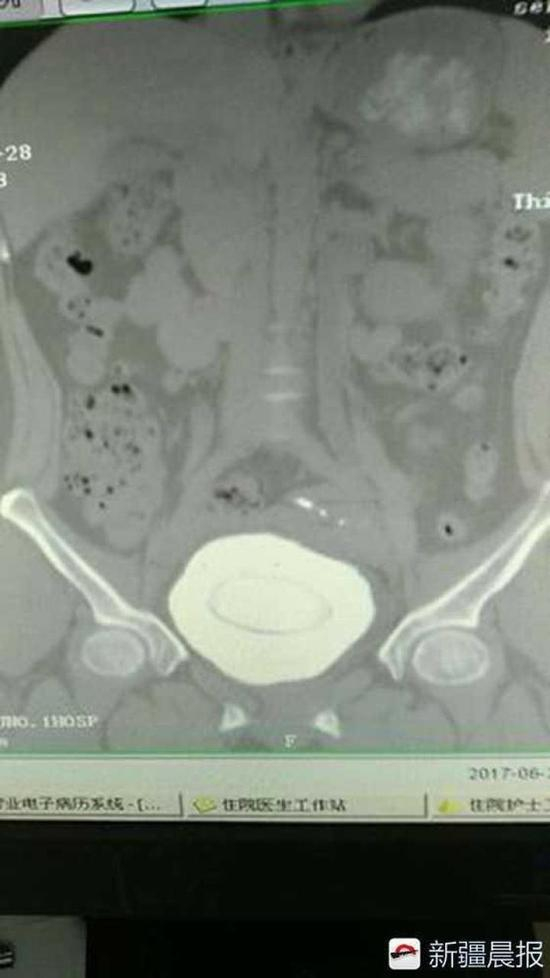

新疆晨报消息,近日,新疆阿克苏地区第一人民医院收治了一位结石患者。医生从患者隆女士的膀胱里取出来的结石,直径约10厘米,760克重,差不多赶上一个铅球大小,如此罕见的一个巨大结石,几乎撑满了隆女士的整个膀胱。

据阿克苏地区第一人民医院泌尿科主治医师刘峰介绍,当时患者隆女士来到医院拍片,腹部CT影像显示,结石占满膀胱,而且结石还有分层,像年轮一样。实际上,隆女士小时候就有结石了,但当时她一直没往这方面想,每次肚子疼时就吃点消炎药。